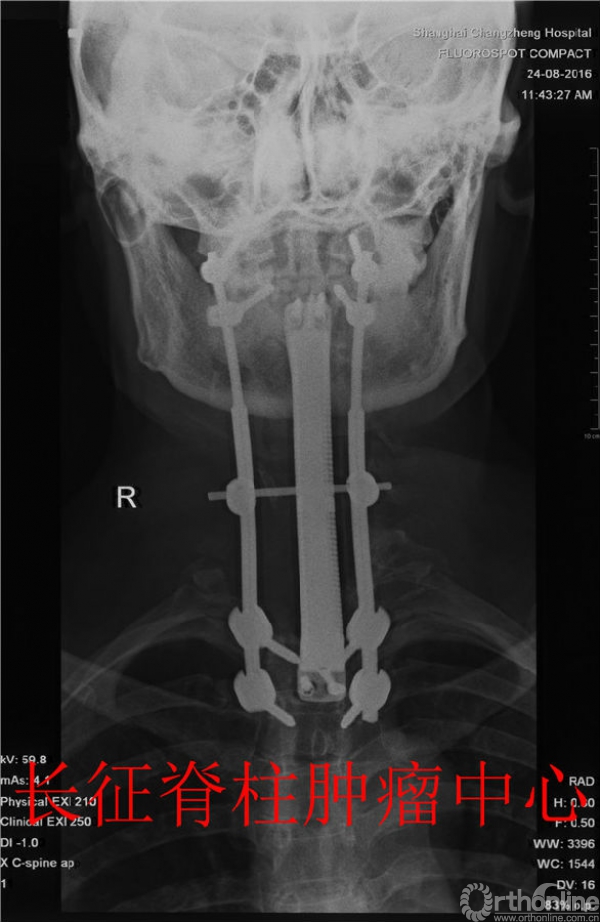

术后X-Ray

在麻醉科的全力配合下,肖建如、杨兴海、赵剑教授等组建的团队先后分二期成功实施了颈前路和后路的手术,经过12小时奋战,成功逾越生命禁区,在放大镜下彻底切除了跨越6个椎节巨大脊索瘤的同时,成功实施了3D打印钛合金6椎节板体一体化假体重建术,重新打开了生命之窗!术后患者症状明显改善,未出现相关并发症,近期顺利出院转至康复医院继续治疗。